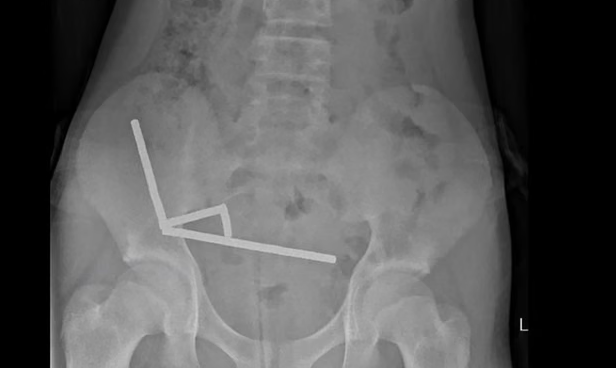

ایک ایکسرے نے دکھایا کہ میگنٹس بچے کی آنتوں کے اندر چار سیدھی لائنوں میں اکٹھے ہو گئے تھے۔ انہوں نے کہا کہ ’یہ مقناطیسی قوت کی وجہ سے آنتوں کے الگ الگ حصوں میں ایک ساتھ چپکے ہوئے دکھائی دیتے ہیں۔‘